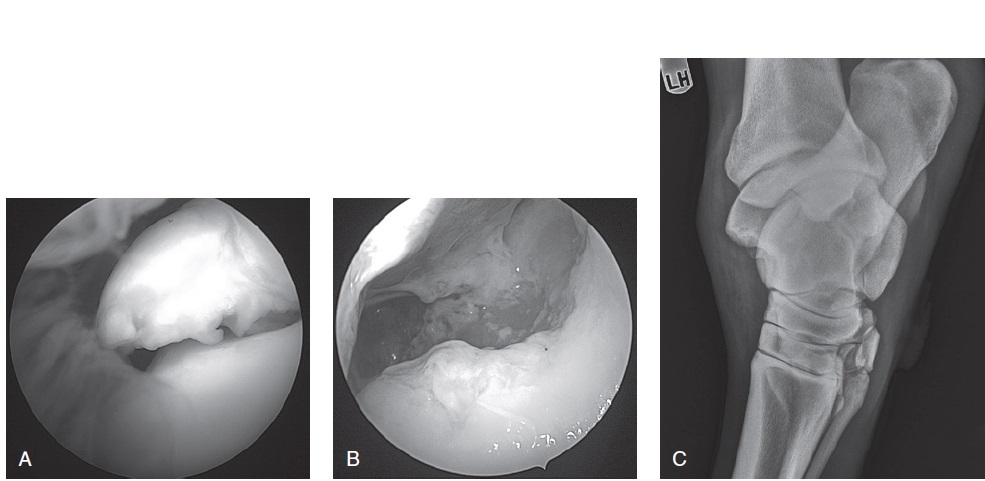

Figure 99-27. Arthroscopic view of a distal intermediate ridge OCD lesion using gas distension (A). The OCD fragment is removed from the distal tibia with the help of an Ethmoid rongeur (B). These OCD fragments are attached in most cases to the tibia by fibrous connective tissue. (C) Graphic illustration of the left tarsus showing the insertion of the arthroscope medially and instrument portal laterally in the dorsal pouch.